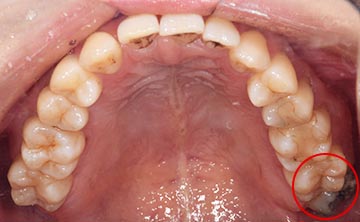

麻布十番歯科で親知らずが横向きに生えて歯ぐきが腫れている症例の口腔内写真のイメージ

抜くのが簡単な親知らずとは